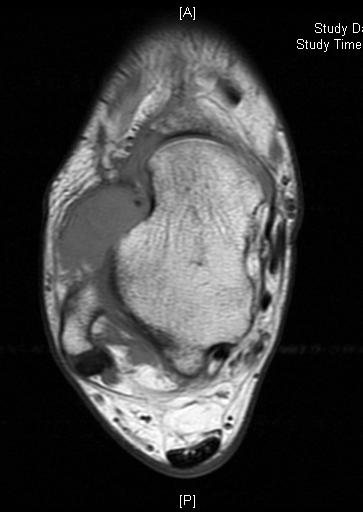

MRI

Shows multiloculated, heterogeneous mass.

“Triple Signal Intensity sign”; hypointense, isointense and hyperintense with fat on T2 – weighted MRI imaging. This sign is present in 30 to 50% of the cases. (Fig.3)

Under contrast enhancement Synovial Sarcoma appears heterogeneous and demonstrate areas of nodular enhancement.

In approximately 30% of cases a multiple vascular cannel may be identified

Synovial sarcomas may have a cystic appearance and are often mistaken for ganglion cysts especially those adjacent to tendons and in the foot and ankle.